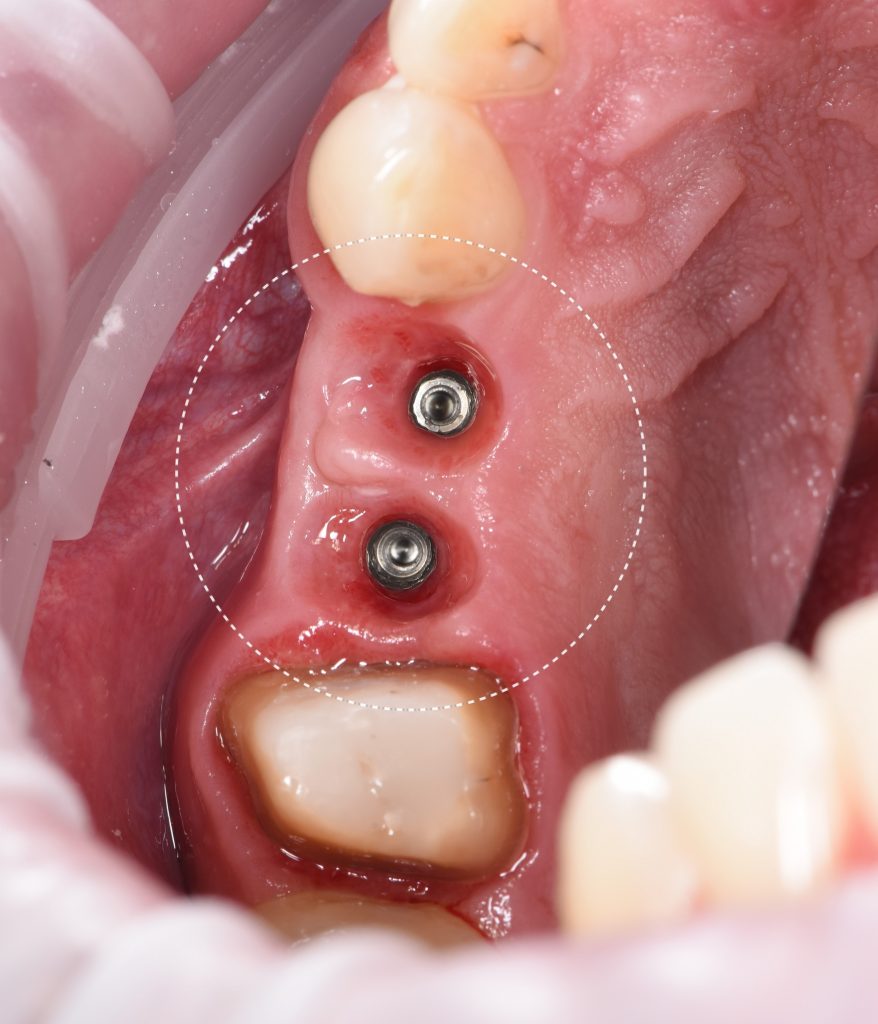

Интраоральная рентгенограмма, загруженная в FMX модуль Diagnocat демонстрирует благоприятную ортопедическую позицию имплантатов